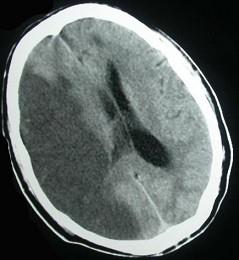

问题 头颅CT出现如图所示脑梗死,该病灶最可能是下列哪条阻塞引起()

选项 A.大脑前动脉主干或大脑中动脉主干 B.颈内动脉主干或大脑中动脉主干 C.大脑中动脉主干或大脑后动脉 D.脉络膜前动脉 E.大脑中动脉深穿支

答案 B